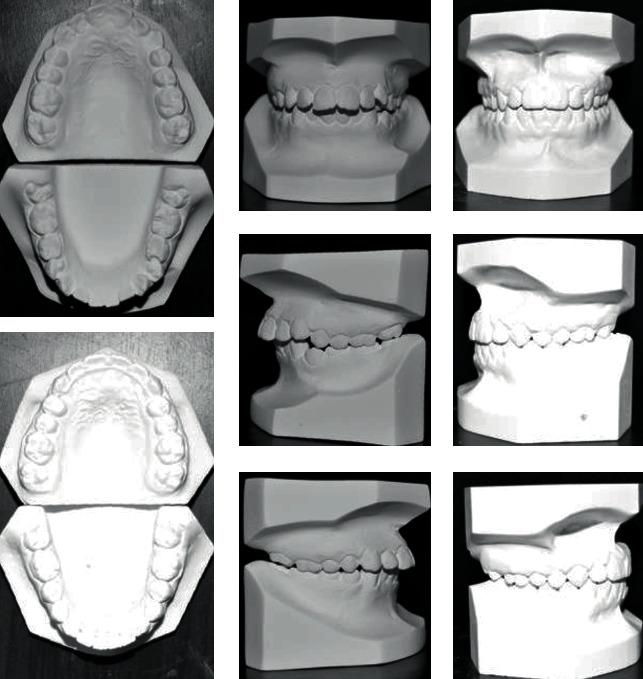

Distalization is a conservative method that is utilized in orthodontics to gain space by moving posterior teeth distally. It may be combined with other space gaining strategies, such as expansion, or can be used alone. Many methods have been used for distalization. These methods differ significantly in their place, whether to be extraoral or intraoral, site of action in upper and/or lower arch, and cooperation needed by the patient if it is removable or fixed. This review illustrates some of the most commonly used methods for distalization with a brief presentation of three cases that incorporated successful distalization techniques.